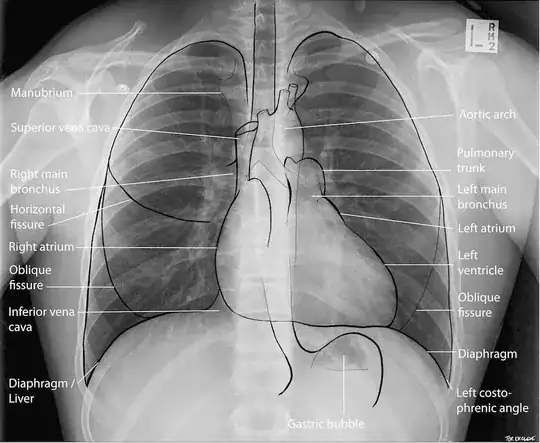

In medical documentation, being an X-ray, MRI, description of physical examination or other, the sides "right" and "left" should be always used from the perspective of the patient. So, the "left neural foramen" is on the patient's left-hand side.

Below is an X-ray image of the chest cavity. You can see the big letter "L" and all the "left" terms on the right side of the image, because this is a view from the front, so they are all point to the left parts of the body. The confusion could occur when someone points to the image and just says "here on the left," without saying "side of the body " or "image." Anyway , when a doctor says something is on the left side, it should be always on your left.

An X-ray image of the chest showing the letter L on the side where the heart is (Source: Lifeinthefastline, CC licence)